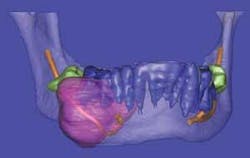

Surface rendering treats the object as if it has a surface of a uniform color. In surface rendering, shading is used to show the location of a light source. Some regions are illuminated, while other regions are darker due to shadows. When surface rendering is combined with volume rendering, it becomes possible to highlight and colorize distinct regions of hard and soft tissues, thus providing a more accurate visualization of borders of pathology to vital structures. Virtual dissection further fine-tunes and pinpoints exact anatomical position.

Stereolithography is also known in the industrial world as rapid prototyping. Dental CBCT scans processed using Sim Plant® software can be digitally transformed for creating stereolithographic models. Rapid prototyping allows the fabrication of physical replicas of 3-D computer-generated models in a layered approach. After the 3-D rendition is generated, software slices the file from top to bottom and then the slice data is sent to a machine that fabricates the part slice by slice. In dentistry, the fabrication of biomodels gives the oral surgeon a full-volume plastic template to plan surgical procedures, fabricate custom-engineered joint- and bone-replacement prostheses, and model facial-plastic reconstructive procedures (see Figures 8a and 8b).